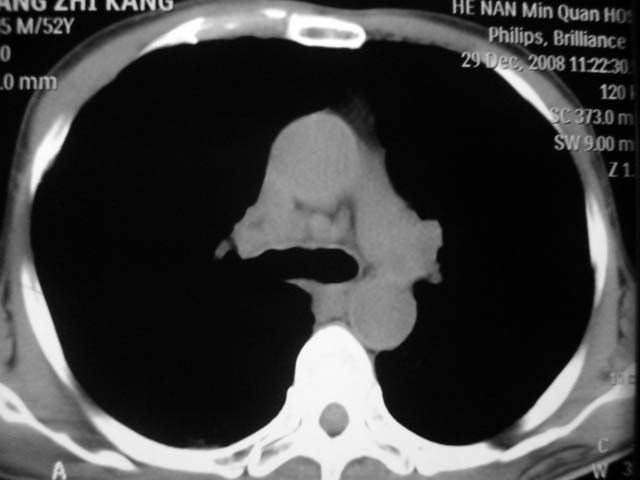

男,52岁,发热2月,糖尿病史。

抗结核治疗irpz方案,血糖未治疗,空腹15.9左右。症状无好转,左胸痛。

复查ct

2、双肺见多发片状及结节状高密度影,大多数病灶中心均见“空泡征”。

3、纵隔内淋巴结肿大。

结果:两肺继发性肺结核并曲霉菌感染。